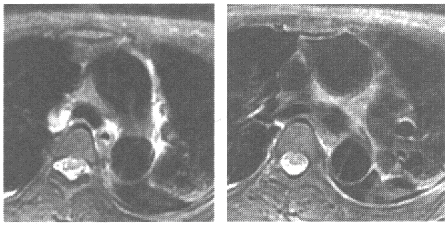

女,胸骨后疼痛3小时就诊,MRI检查如下图,应诊断为

A.主动脉瘤

B.主动脉夹层(DeBakeyⅠ型)

C.主动脉夹层(DeBakeyⅡ型)

D.主动脉夹层(DeBakeyⅢ型)

E.主动脉血栓

女,胸骨后疼痛3小时就诊,MRI检查如下图,应诊断为( )。<br /><img border="0" style="width: 389px; hei

[单选题]女,胸骨后疼痛3小时就诊,MRI检查如下图,应诊断为( )。A.主动脉瘤B.主动脉夹层(DEBAKEYⅠ型)C.主动脉夹层(DEBAKEYⅡ型)D.主